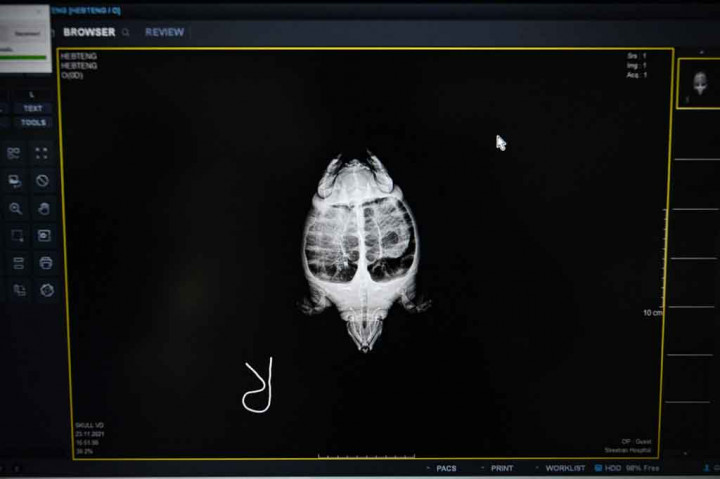

"Dalam 56 persen kasus, penyu yang dibawa ke kami menelan limbah laut atau terperangkap di dalamnya," kata Dr Patcharaporn Kaewong dari Pusat Biologi Kelautan Phuket.  AFP PHOTO/Lillian Suwanrumpha